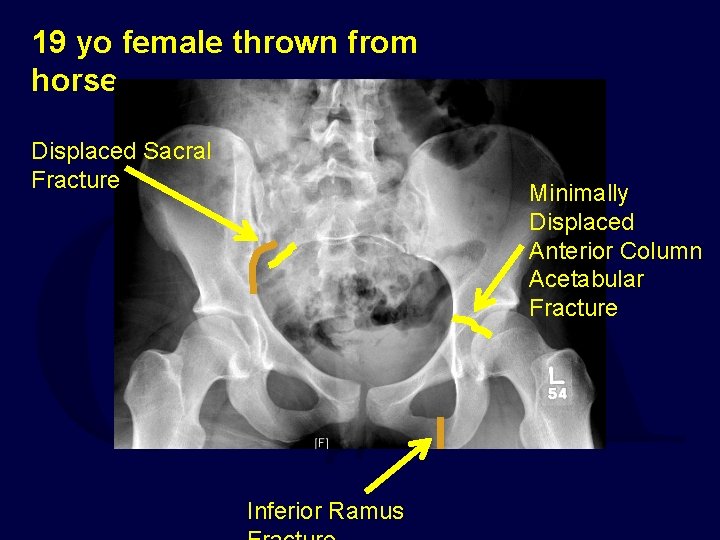

19 yo female thrown from horse Displaced Sacral Fracture Minimally Displaced Anterior Column Acetabular Fracture Inferior Ramus